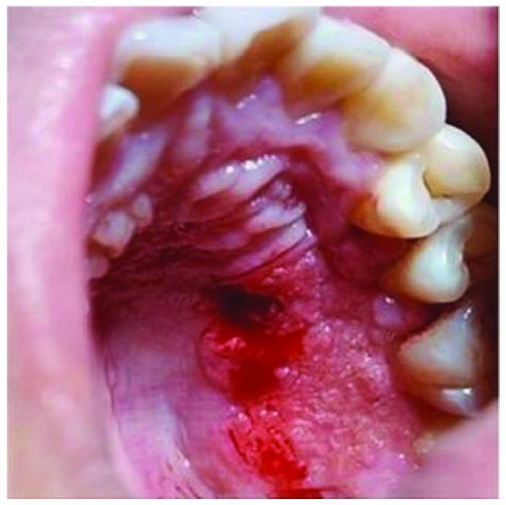

误诊为坏死性肉芽肿的结外NK/T细胞淋巴瘤1例

病史摘要:46岁男性患者,吸烟20余年,每天40支。有反复口腔溃疡史。因腭部溃疡1月余伴发热1周就诊。曾在当地医院治疗,效果不佳。无系统性病史、药物过敏史,家族史无特殊。诊疗过程:初诊时口腔检查发现硬腭部有溃疡,血常规多项指标异常。初步诊断为坏死性肉芽肿或重型复发性口腔阿弗他溃疡。进行局部溃疡组织活检,初诊为坏死性肉芽肿。给予药物、雾化、激光等治疗,5日后复诊溃疡无明显变化,后经病